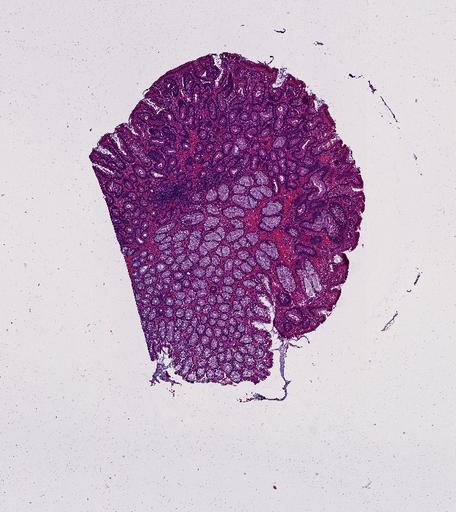

High‑resolution three‑dimensional (3D) tissue atlases promise to redefine how we study cellular architecture‑function relationships in human tissues. Large-scale consortia such as the Human Bimolecular Atlas Program (HuBMAP) systematically build detailed 3D organ maps by profiling serial tissue sections with single-cell spatial technologies. However, an accurate and efficient reconstruction method that can handle atlas-scale datasets remains elusive. We introduce Space-map, an open-source method that integrates single‑cell coordinates with optional histological image features to assemble serial sections into 3D models. Space‑map combines multi‑scale feature matching with large‑deformation diffeomorphic metric mapping, delivering global reconstructions while preserving local micro‑anatomy. To demonstrate the capability of Space-map, we generated a serially sectioned spatial transcriptomics (Xenium, ~2.9M cells) dataset and a spatial proteomics dataset (CODEX, ~2.4M cells). Applying Space-map to these single-cell spatial maps, we built three 3D models for both diseased (colon polyp) and reference colon tissues. These high-resolution 3D models showcase the intricate structure of the human colon across different states. Space-map is fast and highly efficient. We demonstrated its performance and accuracy using in‑house and public datasets. The result shows that Space‑map is 10 times faster and ~2‑fold more accurate than PASTE and STalign, making 3D atlas reconstruction more accessible. Our study provides a new robust and user-friendly software available at https://github.com/a12910/spacemap that can be easily applied for constructing molecular 3D tissue maps of human organs at single-cell resolution.